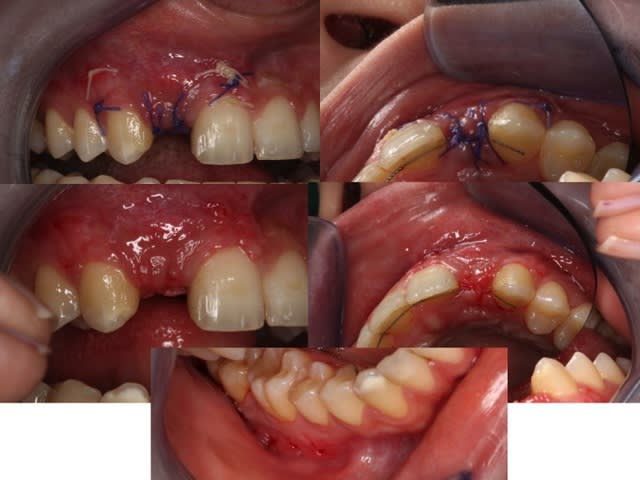

Libération du lambeau avec une lame 15 neuve

Contrôle de la passivité du lambeau en position

Suture et PAP une dent